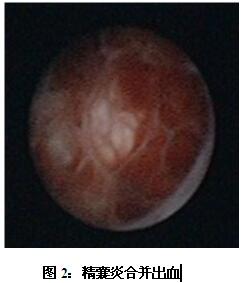

該患者在云南一家三甲醫(yī)院檢查時(shí),發(fā)現(xiàn)雙側(cè)精囊飽滿,質(zhì)地不均勻,考慮精囊炎,經(jīng)輸液抗炎對(duì)癥治療血精不愈,患者及家屬極度緊張,他們通過(guò)熟人介紹來(lái)到我院就診。馬主任經(jīng)過(guò)仔細(xì)檢查,配合超聲、CT、MRI,診斷為“精囊炎、精囊結(jié)石”,認(rèn)為通過(guò)精囊鏡檢查配合局部沖洗、灌藥、碎石才能達(dá)到根治。在中山三院肖恒軍博士的指導(dǎo)及陳日新副主任醫(yī)師、鄧釗晉副主任醫(yī)師以及麻醉科和手術(shù)室的配合下,馬子芳主任為該患者實(shí)施了精囊鏡檢查,發(fā)現(xiàn)患者雙側(cè)精囊內(nèi)充滿結(jié)石和淤積血塊,即予以套石網(wǎng)籃取石和精囊沖洗(如下圖),同時(shí)行囊內(nèi)藥物灌注。術(shù)后2天,經(jīng)直腸彩超復(fù)查,精囊恢復(fù)正常形態(tài)大小,術(shù)后4天治愈出院。